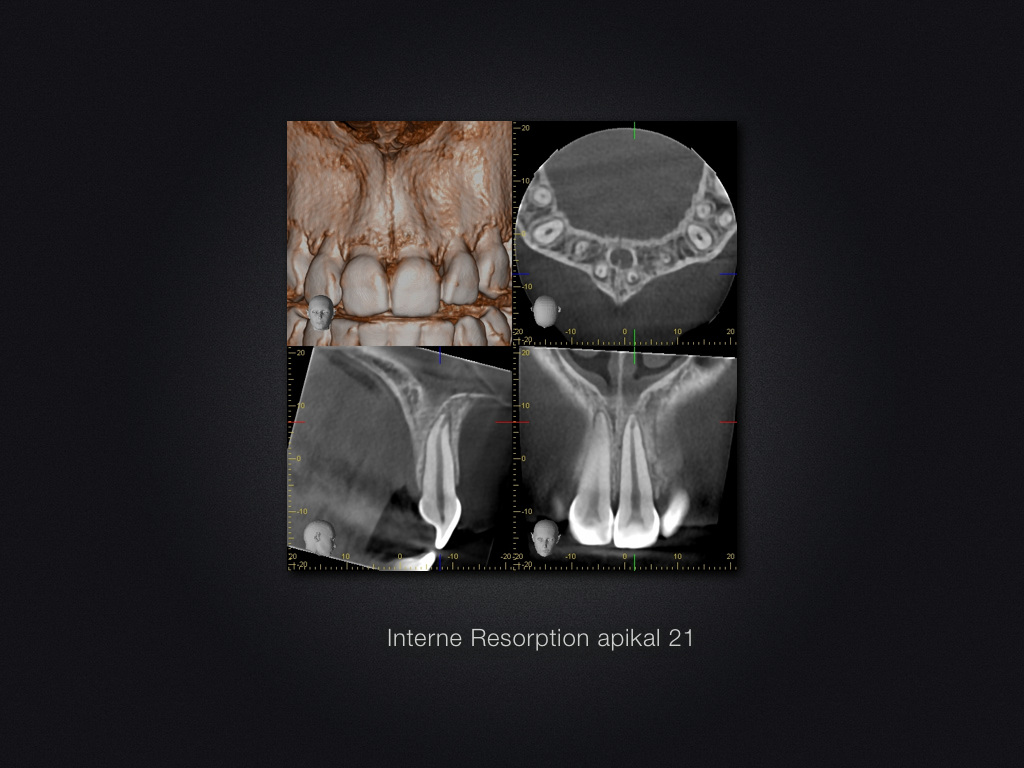

Interne Resorption nach KFO-Therapie